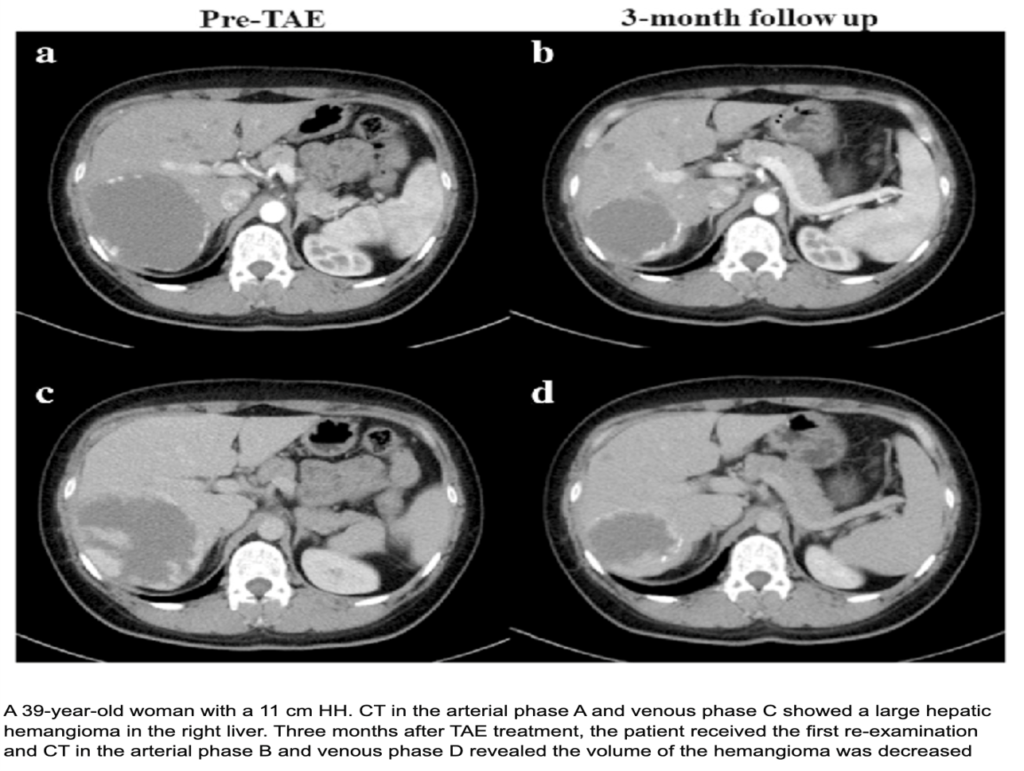

–Well-defined hypodense lesion on NCCT

–Peripheral nodular discontinuous arterial enhancement

–Progressive centripetal fill-in on delayed phase

–No washout, no capsule